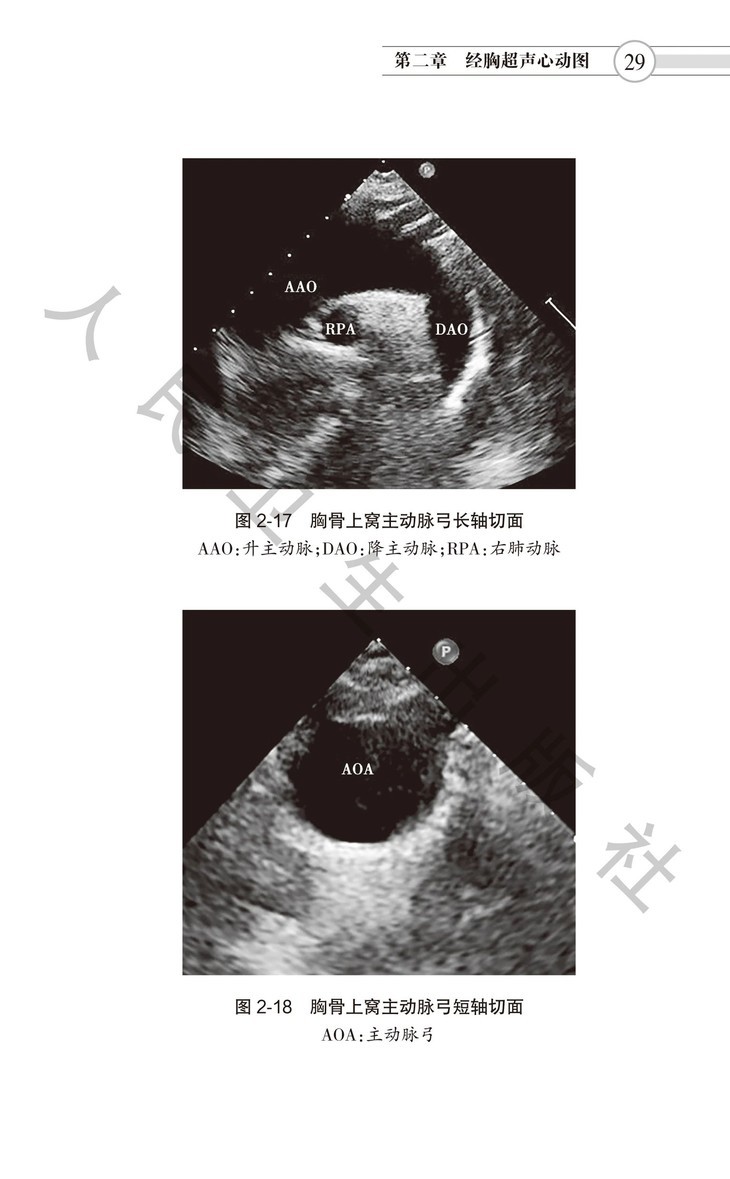

本书是中国医师协会超声医师分会组织编写,邀请众多国内一流心脏超声专家参与、研究和讨论,在2016年出版的《超声心动图检查指南》基础上修订而成。本指南分为七章。涵盖经胸超声、经食管超声、右心造影、负荷超声、床旁超声心动图等各类技术,尤其是超声心动图在各种常见心血管疾病诊断中的应用。涉及超声心动图检查适应证、禁忌证、 检查要点、注意事项和超声报告结论须涵盖内容等,旨在规范超声医师检查行为,适合各年资医师学习阅读,是指导超声医师临床工作的规范性用书。